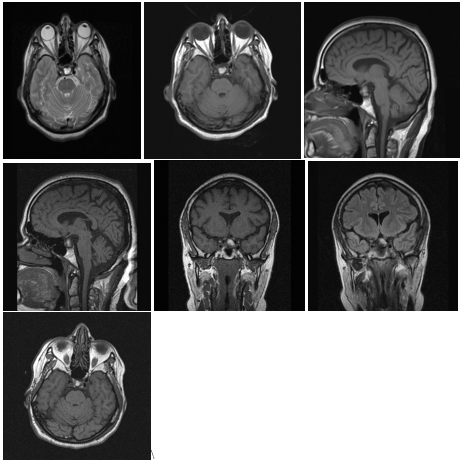

Craniopharyngiomas are rare, benign tumors of the central nervous system. They are epithelial tumors that invariably arise in the suprasellar area of the brain, ascending to involve the hypothalamus, optic chiasm, cranial nerves, third ventricle, and major blood vessels (Figure 1a&1b).

It might present with a wide variety of symptoms, from headaches, nausea, and vomiting to visual and endocrine disturbances. It creates appreciable challenges for the treating physicians. Curative surgeries are generally unattainable and complicated due to their location and infiltration into the vicinity of surrounding structures. Furthermore, the quality of life is generally jeopardized due to the development of multiple complications: panhypopituitarism, visual problems, obesity, and mental disorders (Figure 1a). 2–4

The well-recognized topography of a craniopharyngioma is of either seller or para-seller partially solid mass, cystic, or calcified mass (Figure 2).

A CT scan can show calcification better than other imaging, while MRI can appreciably delineate the extent of the tumor and its relation to the hypothalamus and adjacent structures, therefore, it is sound imaging preoperatively; moreover, MRA can differentiate the tumor mass from vascular malformations like aneurysm (Figure 2).15,16